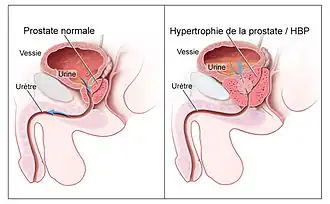

L'hypertrophie bénigne de la prostate aussi appelée hyperplasie bénigne de la prostate (HBP) ou hyperplasie adénomyomateuse de la prostate ou plus communément adénome de la prostate est une tumeur bénigne induisant une augmentation de volume des lobes médian et latéraux de la prostate. Elle touche les sujets âgés de plus de 50 ans.

En cas d'hypertrophie bénigne de la prostate, la prostate devient plus grande et exerce plus de pression sur l'urètre et la vessie, interférant ainsi avec l'écoulement normal de l'urine.

L'hypertrophie bénigne de la prostate affecte la zone transitionnelle de la prostate et provoque une obstruction de l'urètre, ce qui freine l'évacuation de l'urine par la vessie.